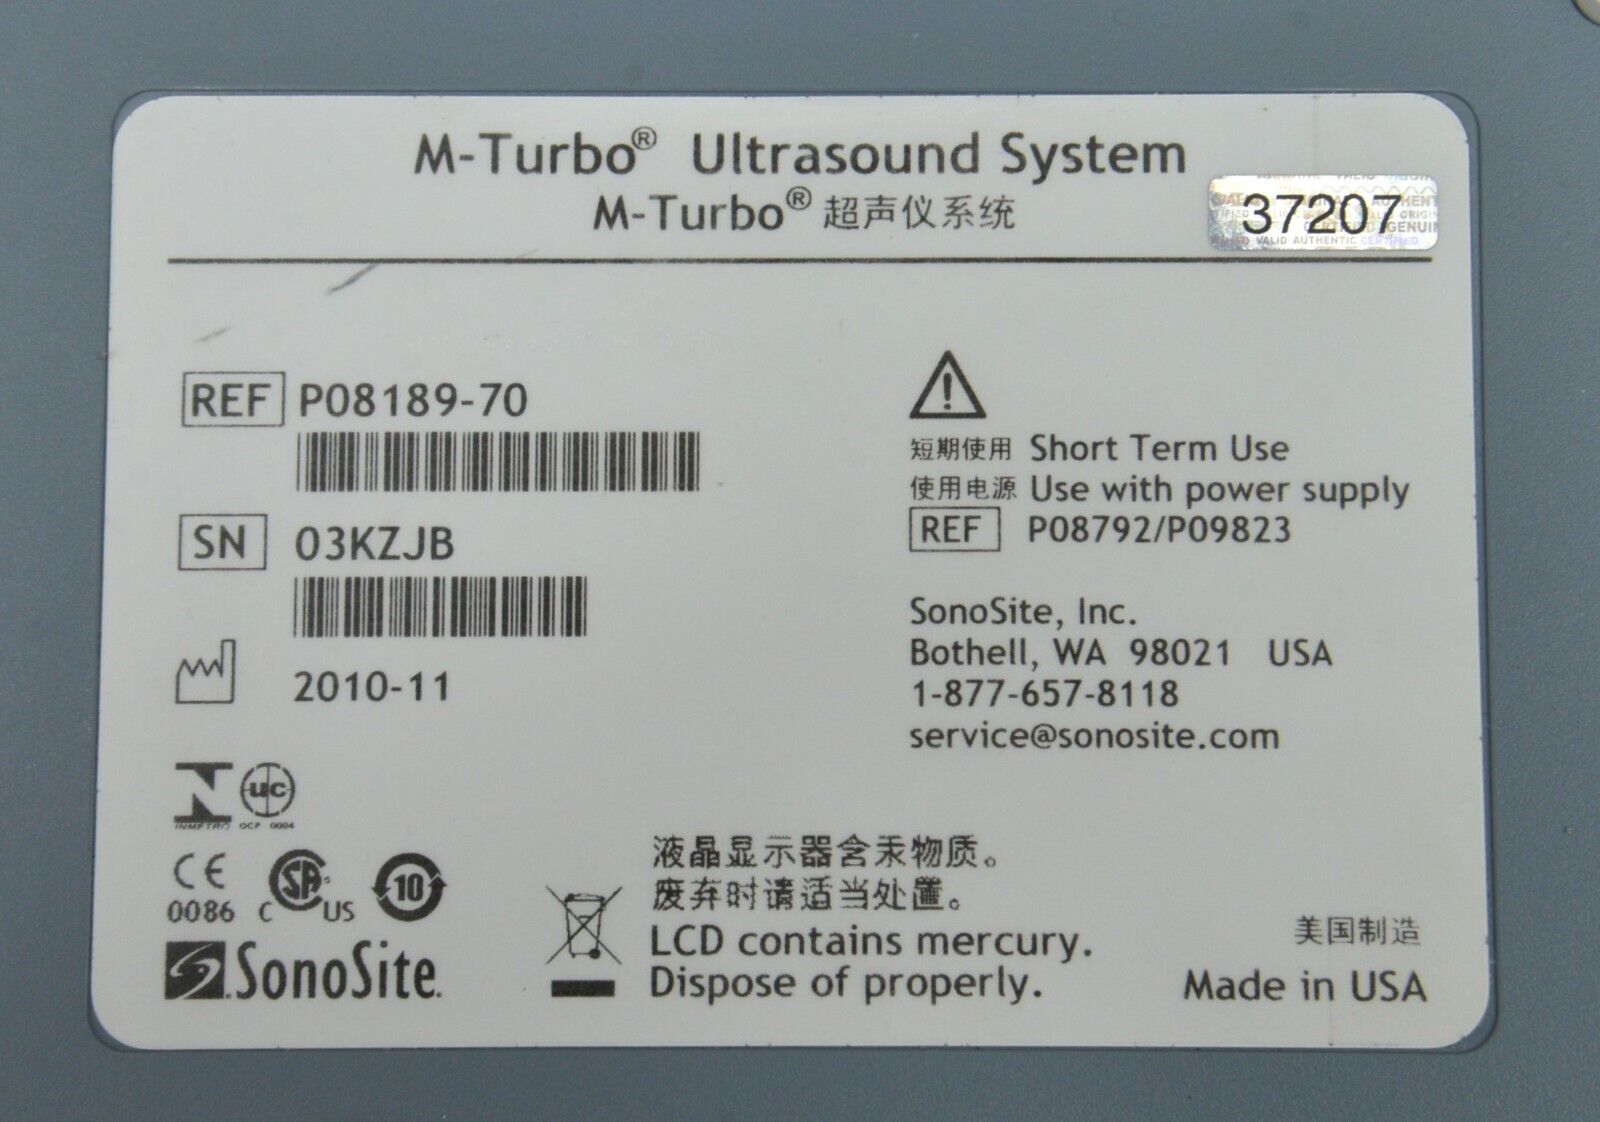

- Fujifilm Sonosite M-Turbo Ultrasound System W/ SonoSite P21x/5-1 MHz Transducer

January 15, 2025Fujifilm Sonosite M-Turbo Ultrasound System W/ SonoSite P21x/5-1 MHz Transducer

Fujifilm Sonosite M-Turbo Ultrasound System W/ SonoSite P21x/5-1 MHz Transducer

This Fujifilm Sonosite M-Turbo Ultrasound System W/ SonoSite P21x/5-1 MHz Transducer is in good working condition. This unit powers on properly and the display screen produces a clear picture. The buttons respond properly to selection and the connections are clean and in good condition. The battery holds a charge. There are a few minor scuff marks from previous use (see photos). This item comes with a 30 day satisfaction guarantee. Includes everything displayed in the photos and nothing else.